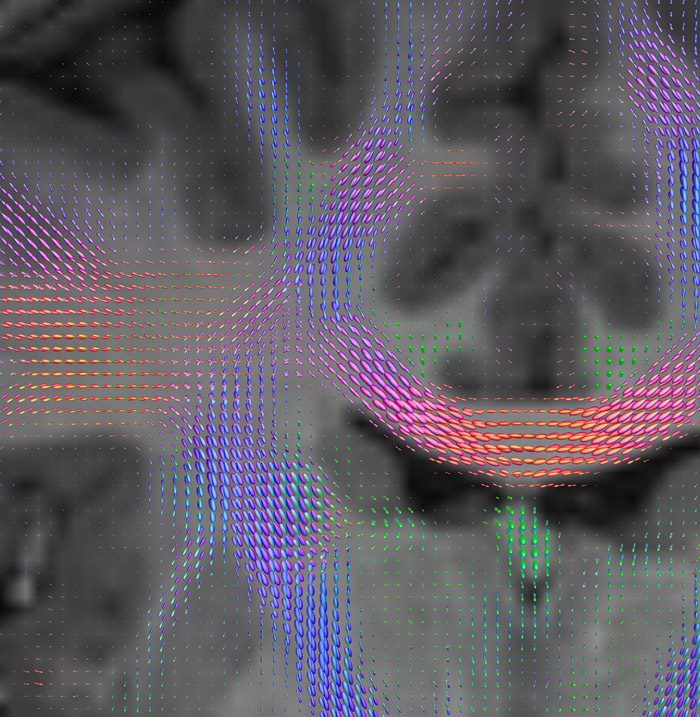

Fiber orientation density

CSD of multishell DWI results in the white matter FOD at each voxel. Unlike the conventional diffusion tensor model, this approach enables accurate modeling of multiple fiber populations within a single voxel.

UVM research fiber orientation density

Crossings of the corpus callosum, corticospinal tracts, and the superior longitudinal fasciculus are shown.

Crossing fibers of the corpus callosum bordered by the superior longitudinal fasciculus as well as within in the pons.